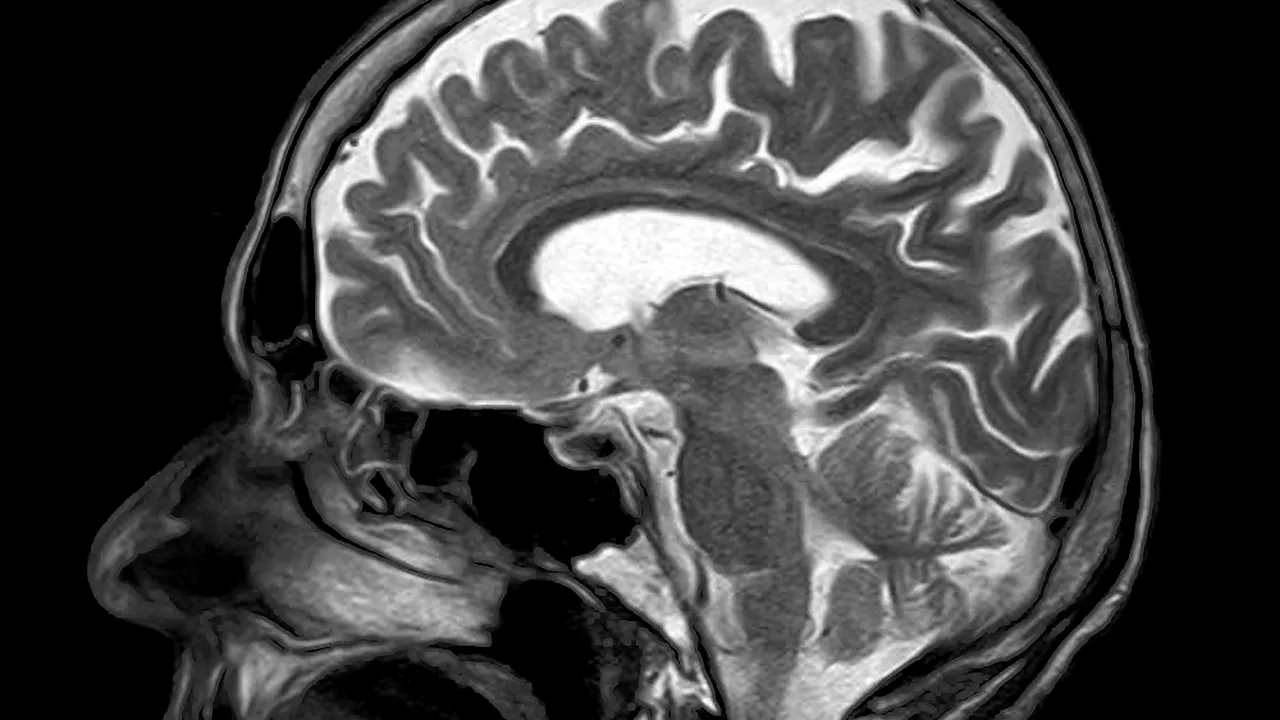

Un scan RMN a arătat activitatea din creierul unei persoane în timp ce lua decizia dacă să facă effort sau nu. Cercetătorii consideră că există diferențe între creierul unei persoane apatice și cel al oamenilor care preferă acțiunea.

40 de voluntari au fost monitorizați în timp ce luau decizia de a face efort pentru a primi o recompensă. Scanurile au arătat diferențe în creierele celor care au avut un scor scăzut la un chestionar care indica nivelul general de motivație.

Când oamenii se hotărăsc să facă anumite lucruri, cortexul premotor are tendința de a se ilumina înaintea activării altor locuri din creier care controlează mișcarea, explică cercetătorii. În cazul celor apatici care luau decizia de a face sau nu un lucru, cortexul premotor s-a aprins mai mult decât la cei obișnuiți cu acțiunea, scrie Live Science.

Oamenii de știință interpretează acest lucru prin faptul că acele conexiuni ale creierului care sunt responsabile trecerea de la luarea unei decizii la acțiunea în sine sunt mai puțin eficace în cazul oamenilor apatici. Acest lucru înseamnă că creierul acestora trebuie să muncească mai mult pentru a-i face să treacă la acțiune.